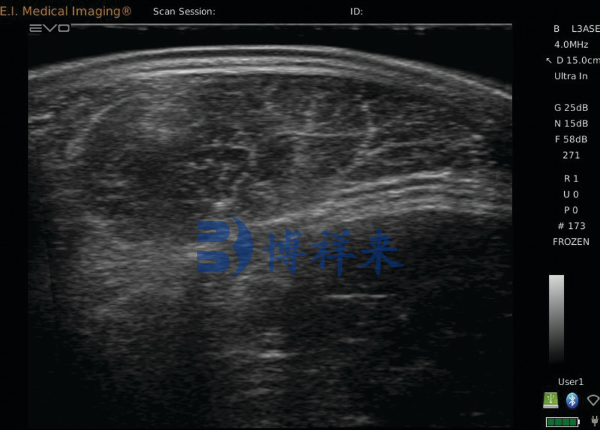

牛用B超,通常是指专为牛只设计的超声波诊断设备,主要通过超声波扫描获取牛体内的图像。这些图像可以实时展示肉牛的肌肉层、脂肪厚度、子宫状况等重要生理信息,帮助养殖者和育种专家做出科学的育种决策。

吉彩网 牛用B超可以精确测定肉牛的脂肪层厚度和肌肉层结构,尤其是在育肥牛的选育过程中,脂肪层和肌肉发育是影响肉质的重要因素。通过实时扫描,育种人员可以评估牛只的肉质潜力,选择出那些脂肪分布合理、肌肉发达的个体,从而提高肉牛的育种价值。

吉彩网 在肉牛育种过程中,牛用B超的应用不仅限于单一的肉质评估,它还可以帮助育种专家判断种牛的繁殖能力。例如,通过B超技术,育种专家能够实时监控母牛的卵巢和子宫状态,判断其是否适合配种。这一信息对于优化种牛选择、提高繁殖成功率具有重要意义。